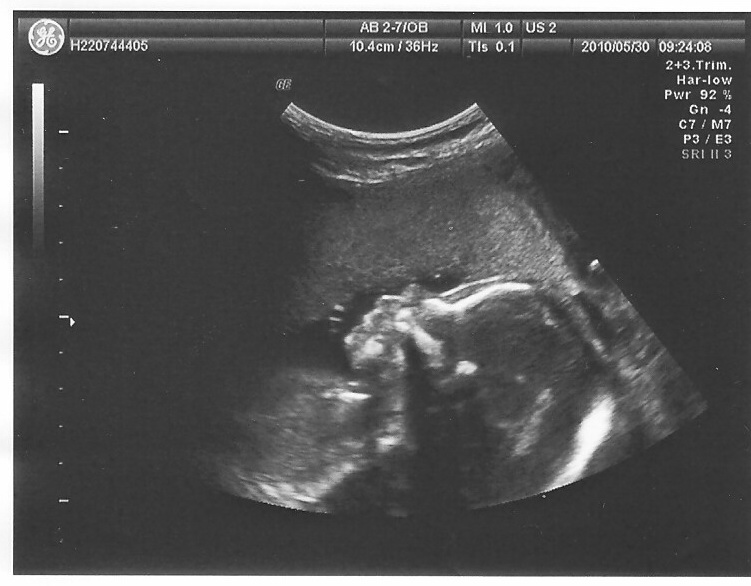

5/13/2010

5/30/2010